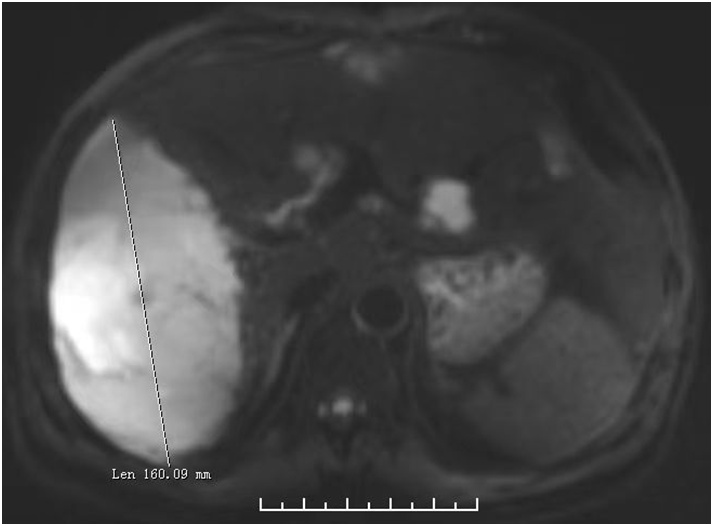

两周前,患者老周急匆匆地赶到杨浦区中心医院就诊,担心自己得了“肝癌”。肝胆胰外科的李桢主任医师在详细了解病情和阅读CT片后,立刻诊断出老周罹患的是肝内多发血管瘤,而非肝癌,这是肝脏内最常见的良性肿瘤,占肝良性肿瘤的84%,中年女性发病率高于男性,是男性的6倍。其中最大的一颗血管瘤的直径足足有16厘米,存在随时破裂出血的风险,宛如一颗“不定时炸弹”,需尽快手术治疗。

肝胆胰外科副主任医师曾和平表示,肝血管瘤直径大于10厘米,称为巨大血管瘤;达到15厘米时,则称为特大血管瘤。体积越巨大,肝血管瘤破裂风险就越大,一旦发生破裂就可能引起生命危险,必须紧急进行医疗救治。手术切除和介入栓塞是目前最常用的两种治疗手段。